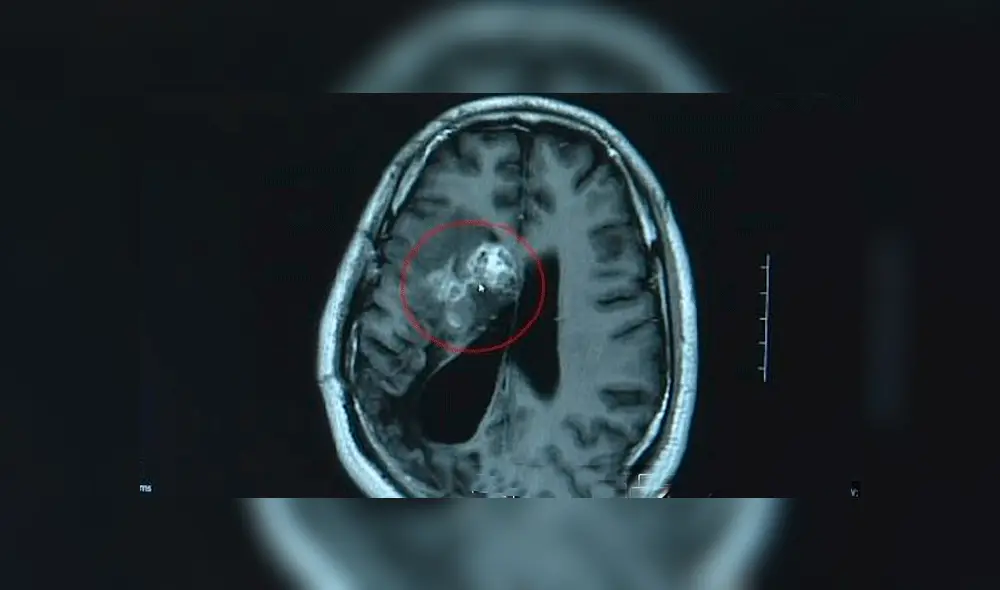

Los doctores, inicialmente le diagnosticaron un tumor maligno y se le dio el tratamiento correspondiente.

Es en este momento que los médicos del Hospital Cerebral de Guangdong deciden realizarle una resonancia magnética y descubren que en su cerebro se alojaba una tenia que medía 13 centímetros de largo y que había comido su cerebro, según informaciones del diario Mail Online.

El Dr. Gu Youming manifestó que el parásito resultó ser un “Sparganum Mansoni”, que suele encontrarse en los intestinos de gatos y perros, rara vez se encuentra en humanos y que tuvieron que operar cuidadosamente, pues el gusano se encontraba vivo.

“Nosotros también teníamos que asegurarnos de eliminar la tenia entera. Si quedaba alguna parte en el cerebro, volvería a crecer”, manifestó el Dr. Gu a los medios de comunicación.